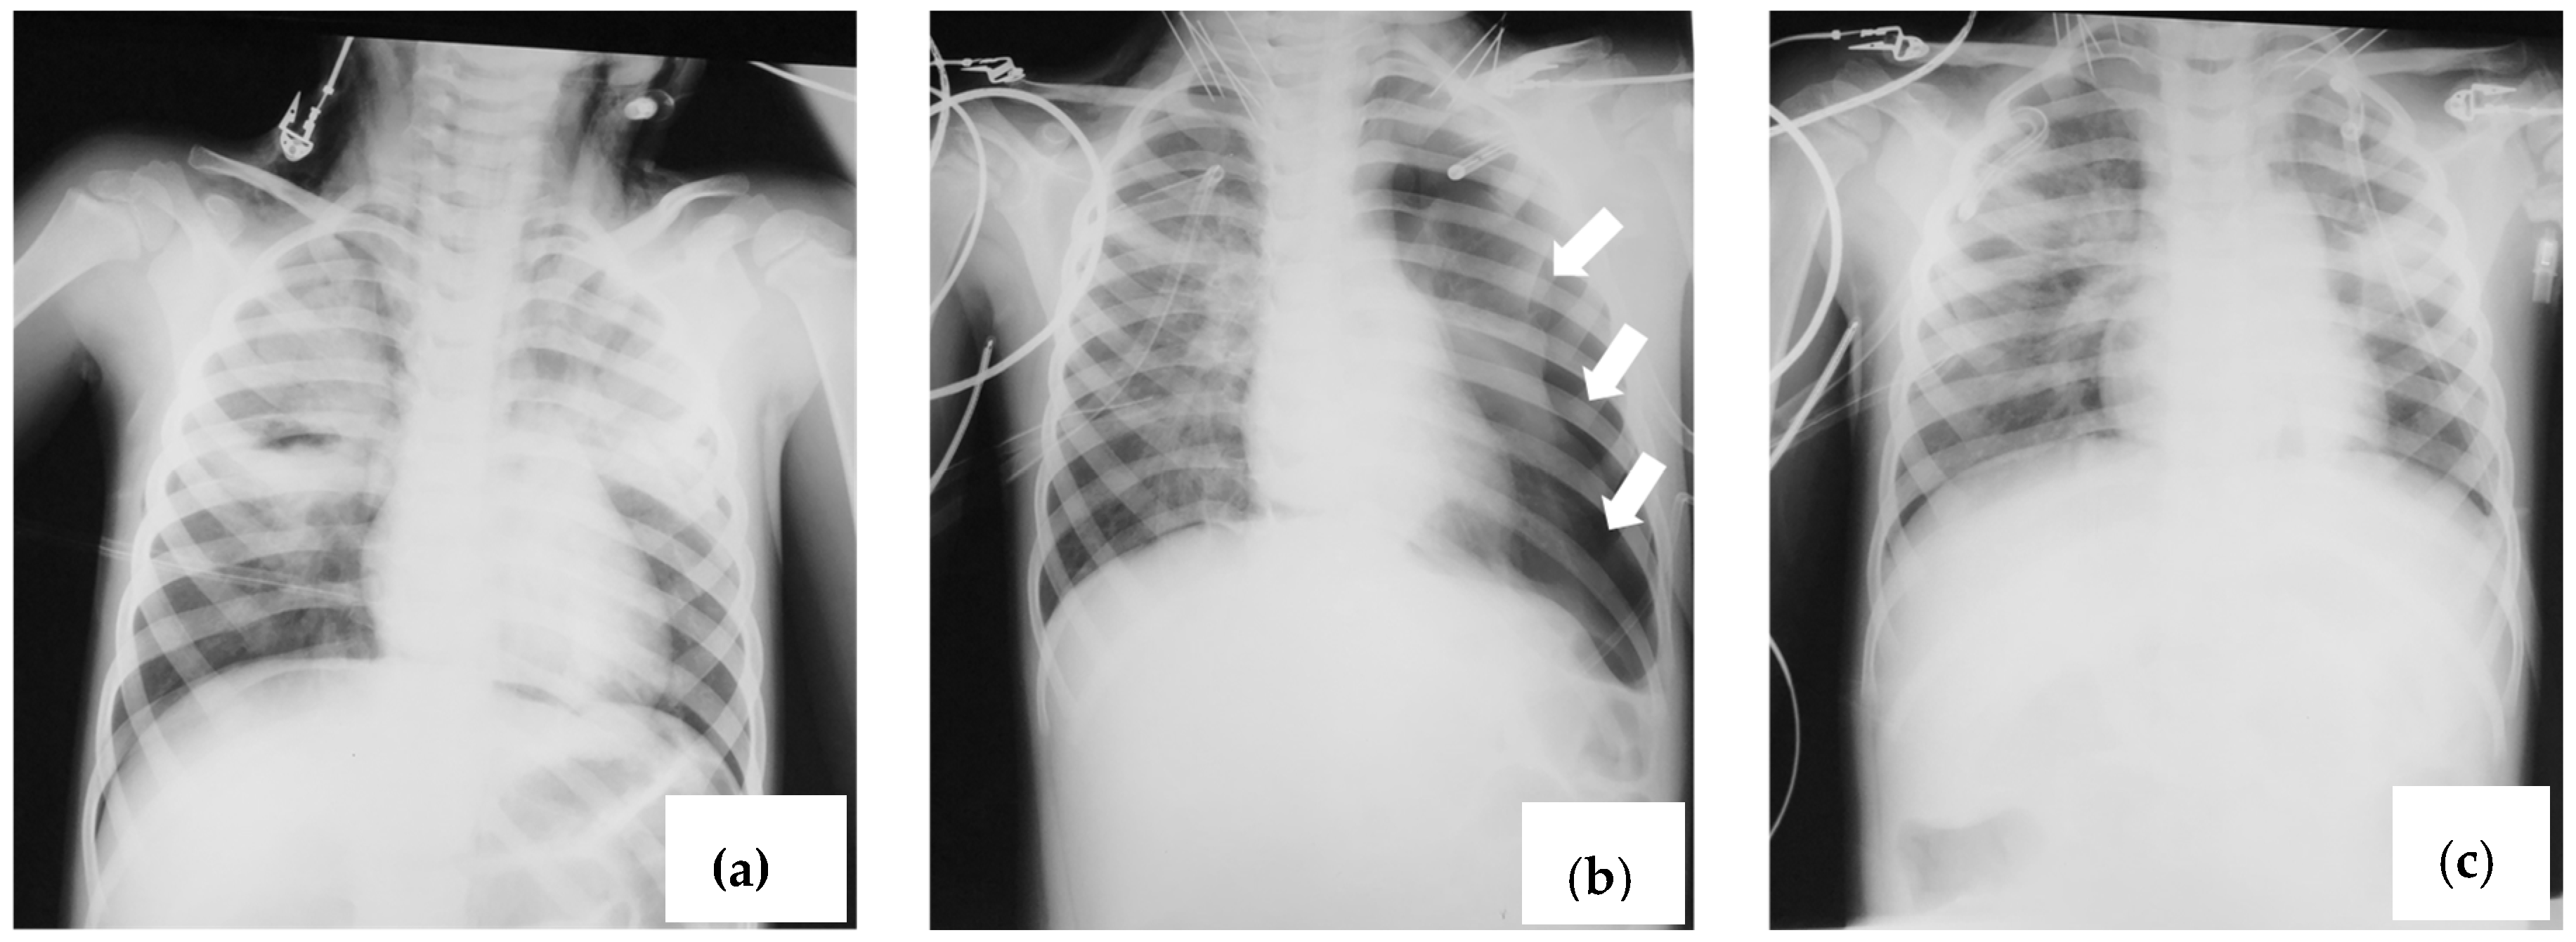

2.2. Case 2

2.3. Case 3

2.4. Case 4